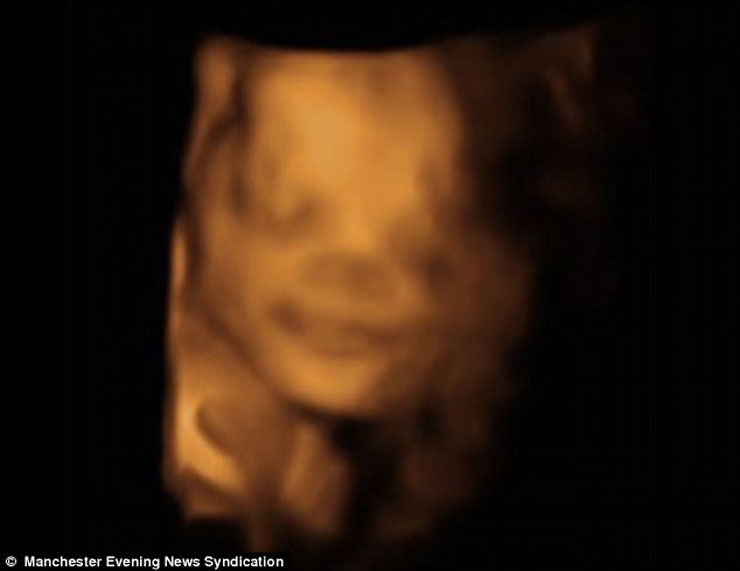

Ένα αγέννητο μωρό εμφανίζεται να… περνάει ευχάριστα και να γελάει μέσα στην κοιλιά της μητέρας του! Οι σχετικές φωτογραφίες που δημοσίευσε η Daily Mail δημιουργήθηκαν με τεχνολογία 4D η οποία είναι πλέον αρκετά δημοφιλής και αρχίζει να κερδίζει έδαφος συγκριτικά με το κοινό υπερηχογράφημα.

Η βρετανική εφημερίδα αναφέρει ότι πρόκειται για τον γιο του ζευγαριού John και Charlotte Steel από το Manchester.

Oι μελλοντικοί γονείς δήλωσαν έκπληκτοι όταν είδαν τον γιο τους να τους χαμογελά, μέσα από την κοιλιά της μαμάς, κατά τη διάρκεια της 31ης εβδομάδας κύησης! Οι εικόνες είναι απλά… μαγικές: